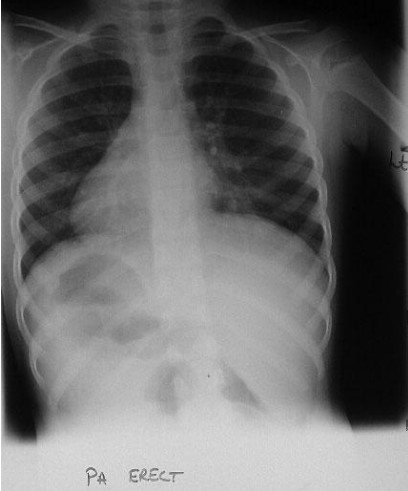

Common X-ray Findings: